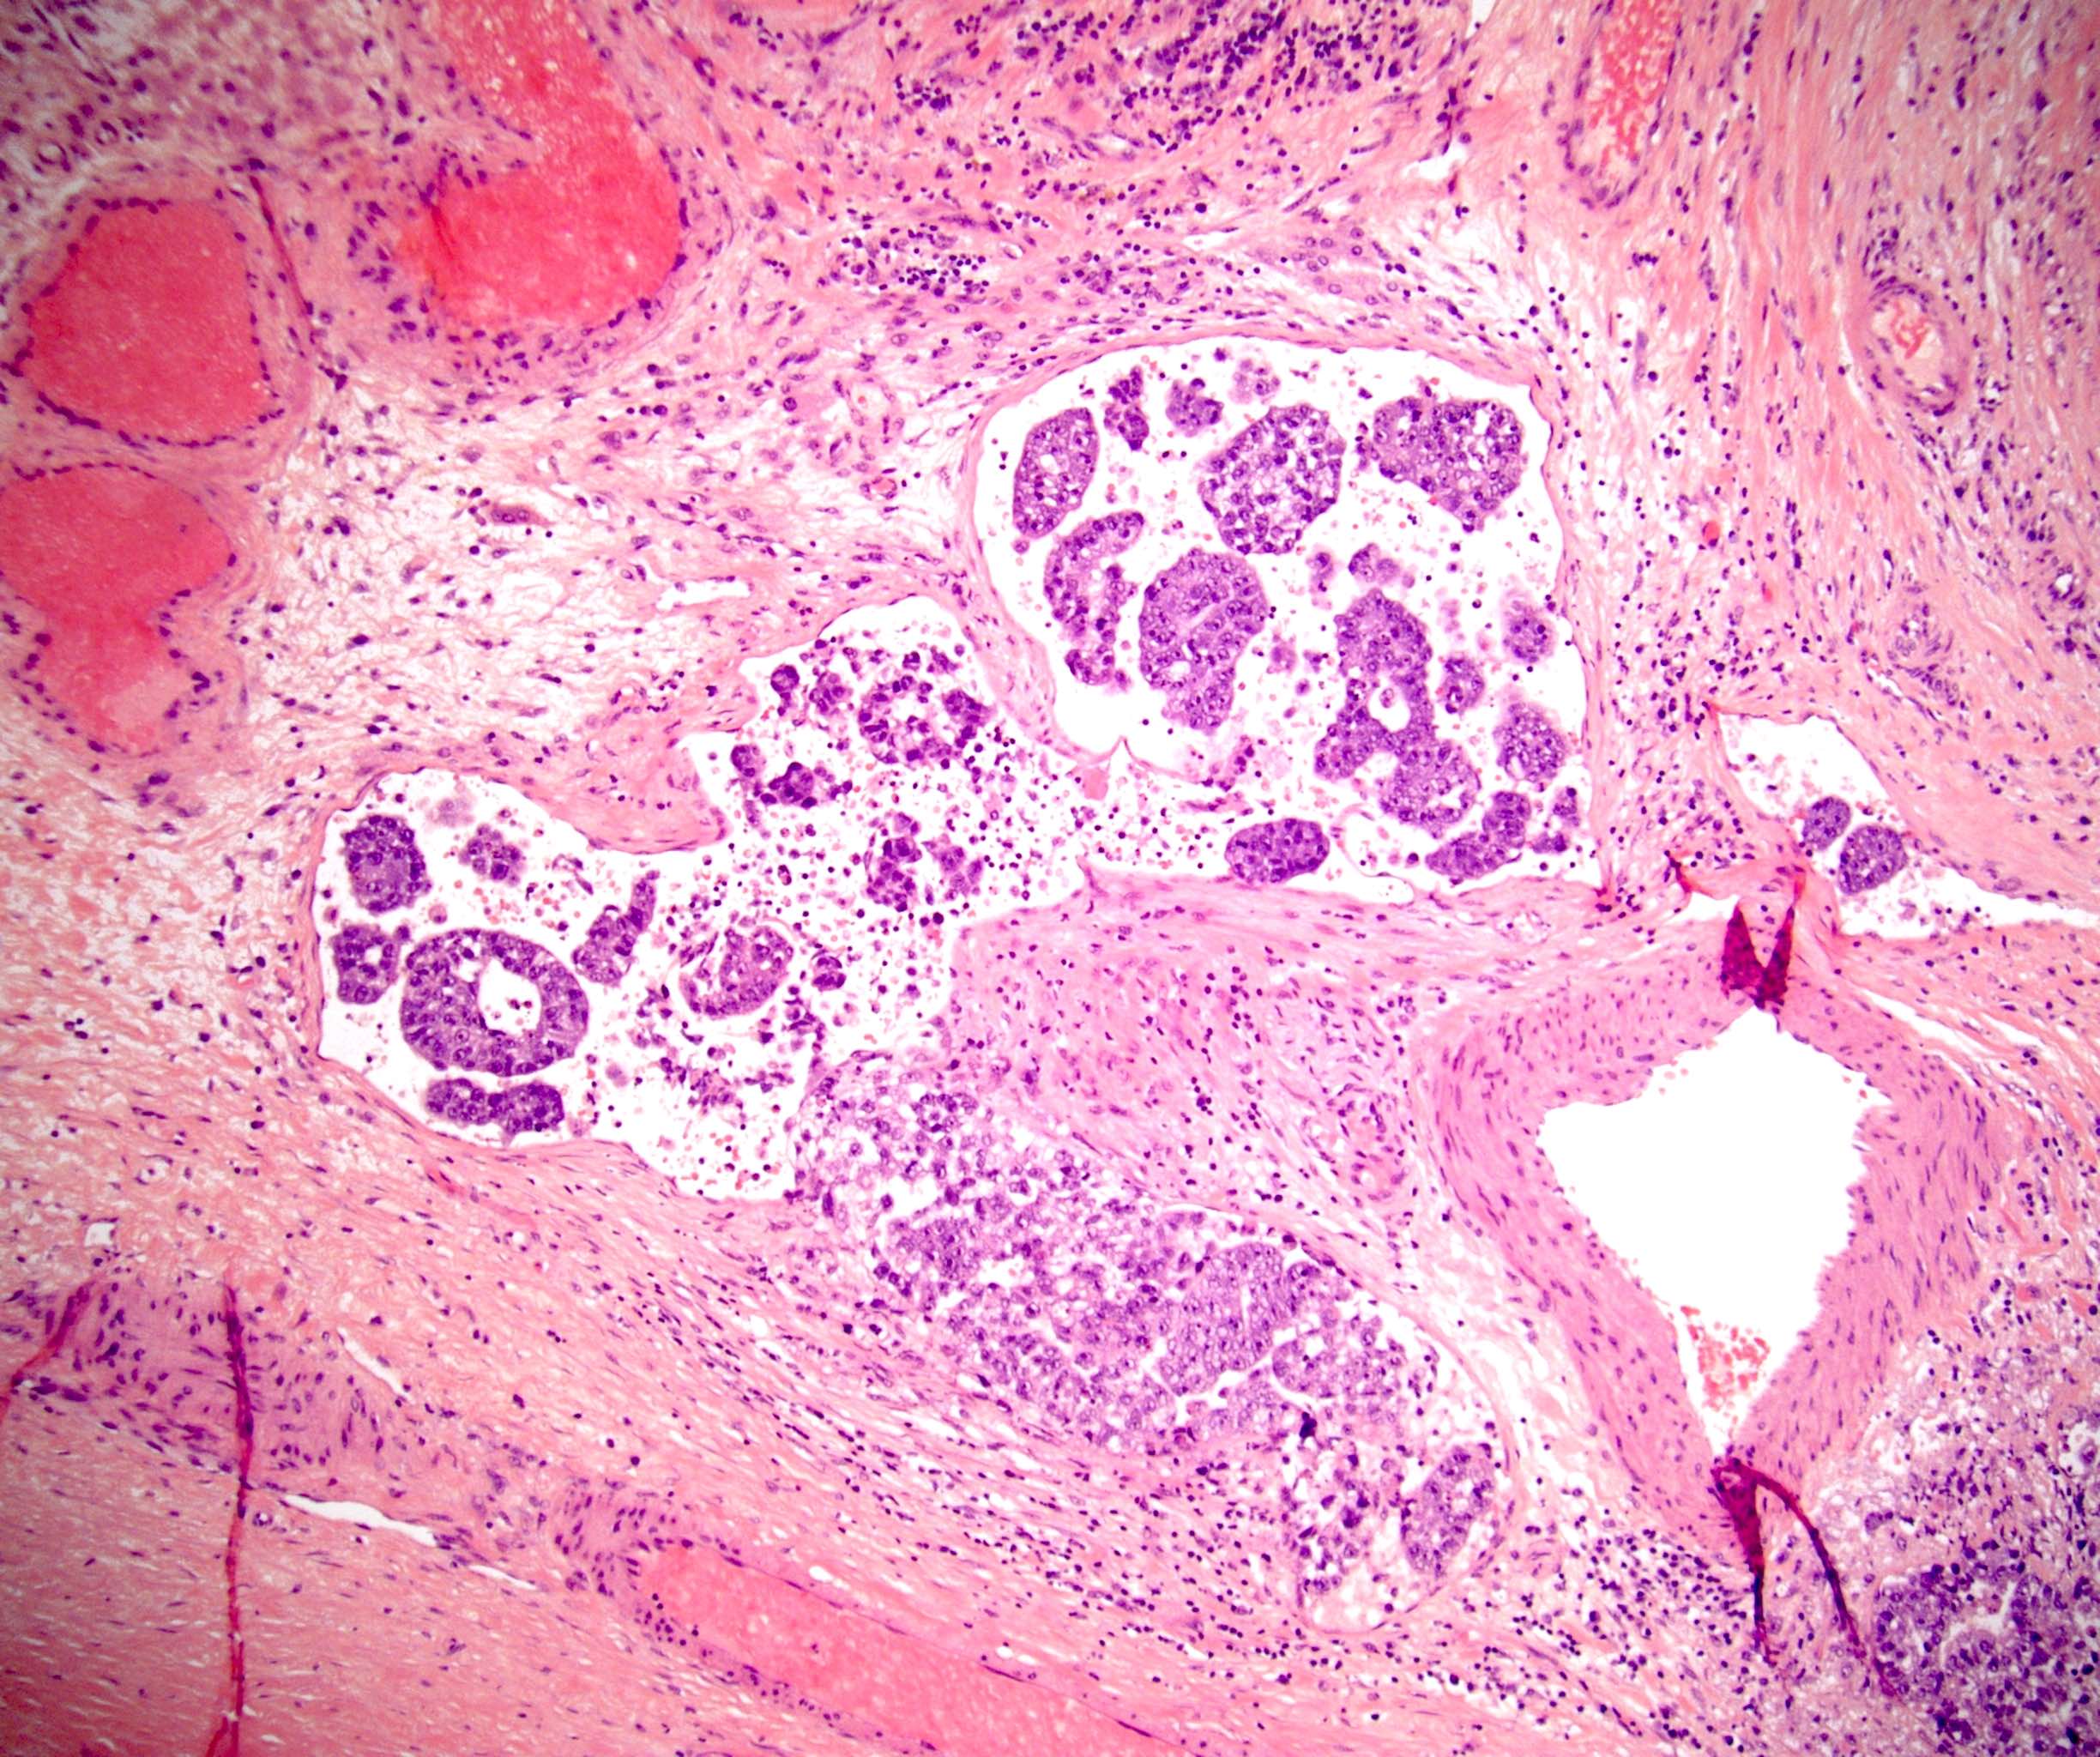

Microscopic (histologic) images

Board review style question #1

In a postpubertal testicular germ cell tumor, lymphovascular (shown above), hilar fat, epididymal and tunica vaginalis invasion are all a part of which pT category?

Board review style answer #1

D. pT2. Lymphovascular, hilar fat, epididymal and tunica vaginalis invasion are all a part of the pT2 category for testicular germ cell tumors. Lymphovascular invasion by embryonal carcinoma is shown in the image.

Comment Here Reference: